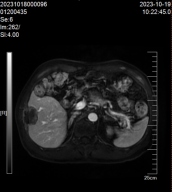

患者,林某某,男性,70岁,既往有乙肝病史,因体检发现肝脏占位入住我院肿瘤内科。入院后肝癌组团队医护立即完善相关检查,肝脏磁共振:肝Ⅵ段见团块状异常信号影,大小约为20mm×16mm×20mm,DWI呈高信号影,增强扫描呈不均匀强化(见图1)。甲胎蛋白(AFP) 1020.00IU/ml,AFP-L3甲胎蛋白异质体:31.20IU/ml,异常凝血酶原测定:341.00 mAU/mL。临床诊断为原发性肝癌,肝癌组卓曼云和张诚胜医生综合分析患者病情指出,患者诊断小肝癌明确,可选择微波消融或手术切除。患者家属考虑年纪大,不愿意手术治疗,遂在CT引导下行肝癌微波消融术。消融术中患者无手术出血,术后无明显不良反应,住院时间短,住院费用少,术后恢复快,1个月后复查肝脏MRI提示完全消融。目前患者定期复查未见复发。

消融前 消融中 消融后